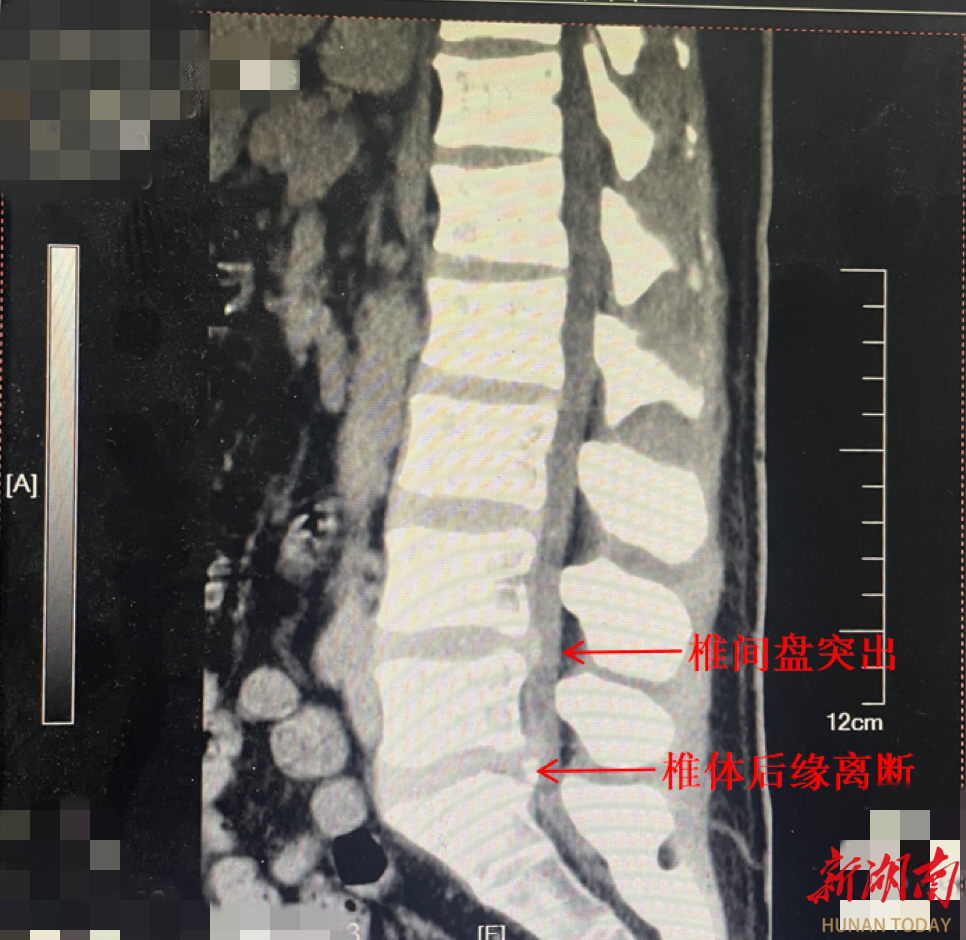

骨科五病区脊柱专科殷浩副主任医师为他进行了详细的检查,最终诊断为:腰椎管狭窄症、腰椎间盘突出、腰椎椎体后缘离断症、腰椎不稳定,很难让人相信这是一位30多岁的年轻人的腰,“腰龄”简直到了60-70岁。

并且,从检查结果可见他的腰椎还出现腰椎椎体后缘离断,也就是椎体骨头边缘断裂,直接扎进神经,导致椎管内神经严重受压。多个问题的堆积,让他的腰椎“摇摇欲坠”,相当于提前衰老了30年。这种情况下,必须尽快手术治疗,再拖下去可能导致神经不可逆损伤,无法行走,以后只能坐轮椅。